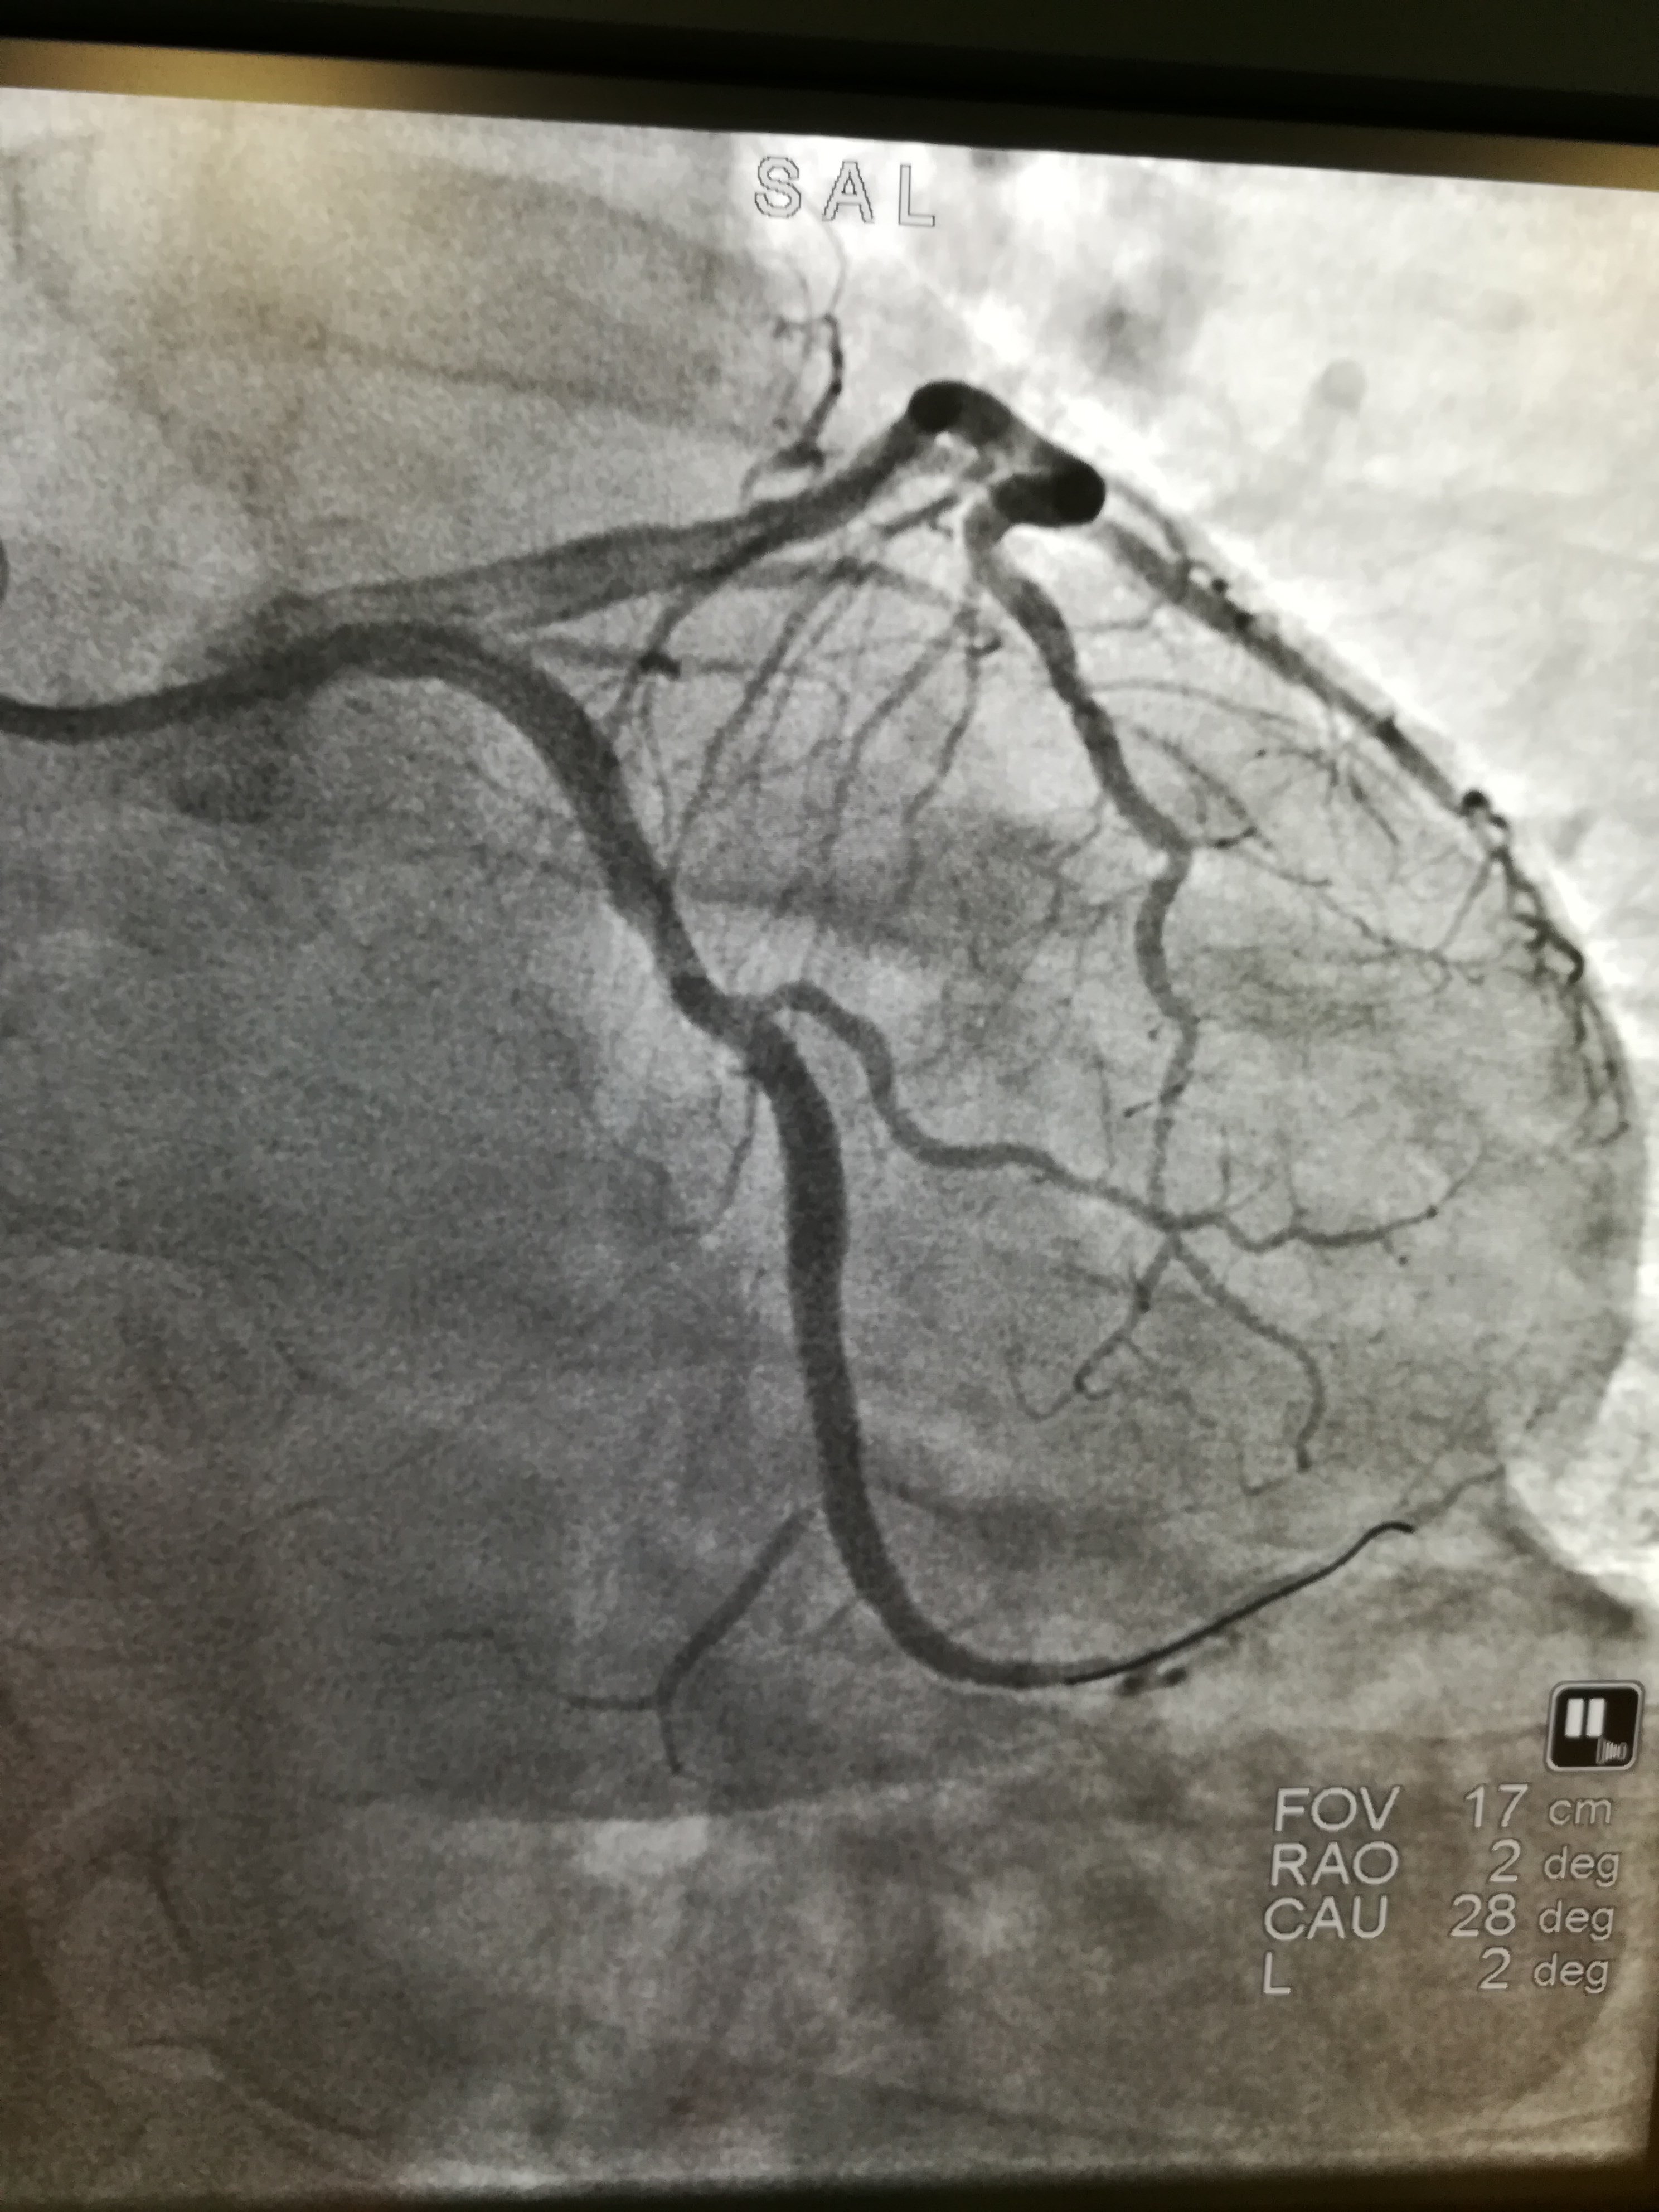

这是最近我抢救的一个急性血管闭塞的病人,也就是俗称的心肌梗死。